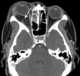

Retrobulbar abscess